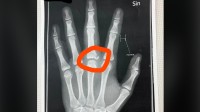

左手骨折仍想冲!玩家晒X光求单手游戏 网友狂甩安利清单